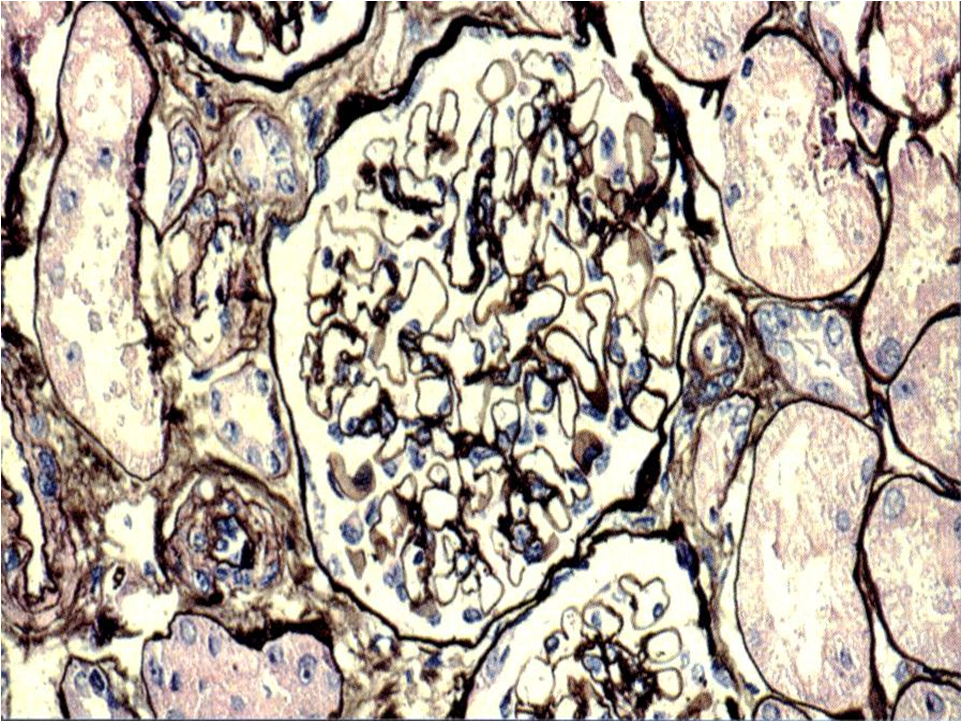

光镜下较常见的病理改变为系膜细胞和系膜基质弥漫重度增生,可插入到肾小球基底膜(GBM)和内皮细胞之间,使毛细血管袢呈“双轨征”。

免疫病理检查常见IgG和C3呈颗粒状系膜区及毛细血管壁沉积。

电镜下系膜区和内皮下可见电子致密物沉积(图5-4-3)。 该病理类型约占我国原发性NS的10%~20%。本病男性多于女性,好发于青壮年。约1/4~1/3患者常在上呼吸道感染后,表现为急性肾炎综合征;约50%~60%患者表现为。NS,几乎所有患者均伴有血尿,其中少数为发作性肉眼血尿;其余少数患者表现为无症状性血尿和蛋白尿。肾功能损害、高血压及贫血出现早,病情多持续进展。50%~70%病例的血清C3持续降低,对提示本病有重要意义。 本病所致NS治疗困难,糖皮质激素及细胞毒药物治疗可能仅对部分儿童病例有效,成人疗效差。病变进展较快,发病10年后约有50%的病例将进展至慢性肾衰竭。